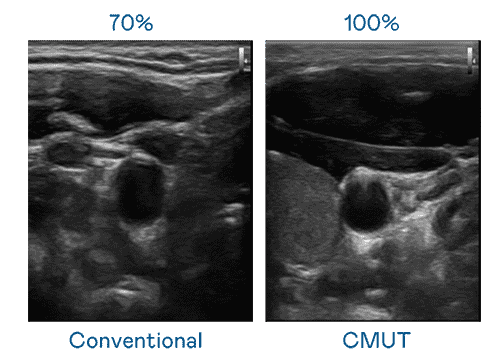

CMUT 技术是一种用电容式微机电元件来产生超音波讯号的技术。。。。与传统 PZT 压电式技术相比,,CMUT 频宽增加 30%,,,,更宽频的超音波讯号让影像解析度大幅提升,,,,是实现高影像品质医疗超音波扫描、、、、促进精准医疗发展的关键技术。。。

大频宽带来超清晰影像

超音波影像的解析度高低,,,首先取决于探头能发出的讯号频宽。。。。至成国际 CMUT 可提供高清晰的超音波讯号,,提供高频宽、、、高灵敏度、、、、影像纹理细节更高的超音波影像,,协助医护人员缩短影像判读时间及利用精准的医疗影像进行诊断。。。